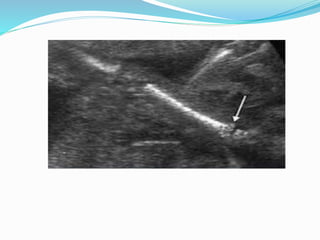

Osteogenesis imperfecta

 Poor bone mineralization

 Types 1-4

 Most common types is type 2

 Short, hypomineralized crumpling bones with

multiple fractures

 Criteria of Diagnosis : 1- Multiple fractures ,

2-hypoechoic skull , 3- Femur length more than 3 SD

below G.A